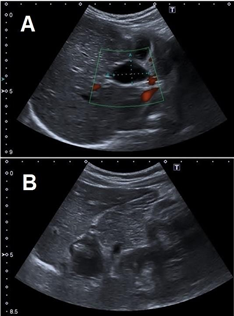

No other symptoms and signs were associated during “attacks”. Laboratory tests were always normal during the episodes. During a new episode (9 year-old) other ultrasound was performed. A cyst was observed in the hepatic hilum and the gallbladder fossa was apparently empty (Figure 1: A, B). Trying to clarify the anatomy a CT-scan was perfomed and an upper gastrointestinal contrast study to rule out a duodenal duplication cyst. Again other Magnetic Resonance Cholangiopancreatography (MRCP) was accomplished (Figure 2).

Figure 1

A: Ultrasound scans showing a Cystic formation in the hepatic hilum.

B: Gallbladder fossa apparently empty, suggestive of “atrophic gallbladder”.